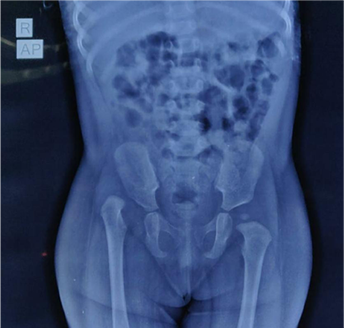

Before

Pre operative X ray showing Right hip dislocation